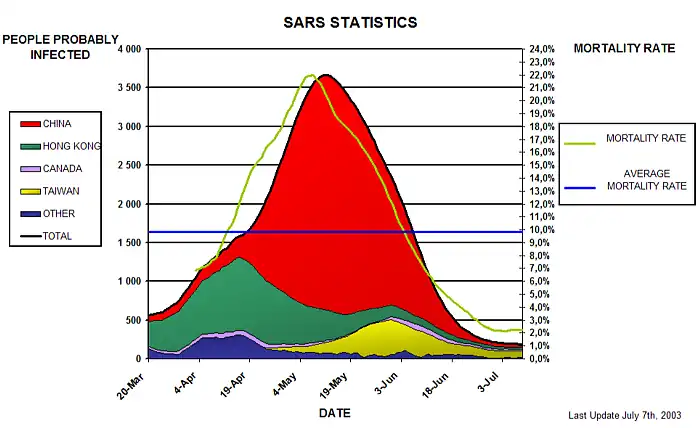

Este gráfico representa la evolución de la persona con probable infección, de varios países y los ratios de mortalidad en las 2 últimas semanas.- .- Persona probablemente infectada = Caso acumulado - Número de fallecimientos- - número de altas. - Razón de mortalidad = Muertes / (Muertes + Altas) - (Fuente : WHO WEB SITE. Puesta al día 06/07/03)